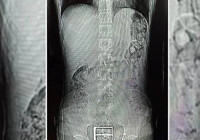

Midesinden ve bağırsaklarından bakın ne çıktı Erzurum’da polisin şüphelenerek durdurduğu İran uyruklu kişinin mide ve bağırsaklarından sentetik uyuşturucu çıktı. Şüpheli, çıkarıldığı mahkemede tutuklanarak cezaevine gönderildi.